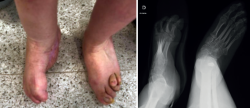

Se trata de una paciente de 34 años en seguimiento en consultas externas por pie zambo derecho congénito. Presenta un tobillo, mediopié y antepié rígidos, un pie equino, varo, aducto y supinado rígido (Figura 1), además de anestesia sensitiva (a consecuencia de lipomeningocele).

Figura 1. Pie zambo derecho con deformidad en equino, varo aducto y supinado.

Sus dedos menores se encuentran en ráfaga media y presenta úlceras periódicas en la base de M5 por hiperapoyo (Figura 2). Además, la paciente nunca había tenido un pie plantígrado.

Figura 2. Pie derecho con apoyo en M5 y dedos en ráfaga medial. Radiografía en carga.